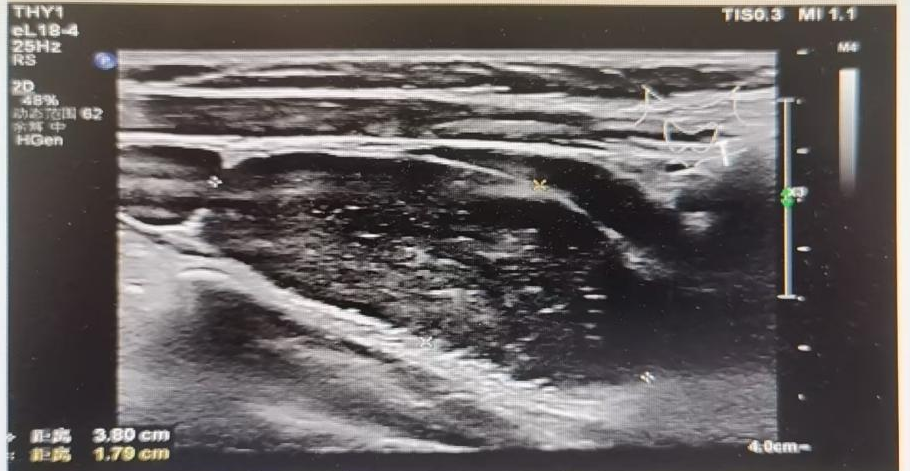

B超(2022.5.17)

▪ 左中上腹实性肿物——考虑恶性,神经母细胞瘤可能性大,大小约12.3×9.9×6.5cm。

▪ 腹膜后多发淋巴结肿大——考虑转移瘤,最大5.1×2.9×2.4cm。

▪ 左颈部多发实性肿物——考虑转移瘤,最大3.8×2.2×1.8cm。